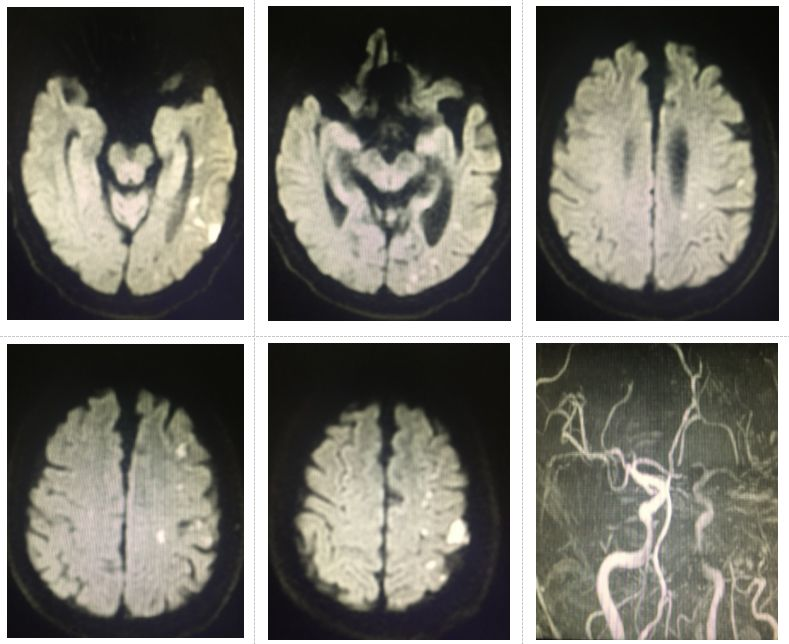

图1.头MRI+MRA示左侧枕、颞、额顶叶多发新近梗塞灶;左侧颈内动脉岩骨段重度狭窄;左侧大脑前动脉、大脑中动脉狭窄;左侧大脑后动脉远端闭塞

患者临床表现为右侧肢体无力、麻木,定位于左侧半球,定性为缺血性脑血管病。头颅MRI+MRA明确为左侧半球前、后循环均有缺血病灶,且颅内段血管多支狭窄/闭塞,符合责任血管的低灌注表现。但真的是这样吗?

仔细阅片,可见左侧颈内动脉岩骨段及颅内段血管似乎存在重度狭窄,但左侧颈内动脉岩骨段以下部位整体血管较对侧颈内动脉偏细,这时我们就有理由怀疑患者的左侧颈内动脉起始部可能也存在狭窄,且患者查体时听诊可闻及左侧颈动脉杂音。到底是不是这样呢?于是,我们预约了颈动脉超声检查。